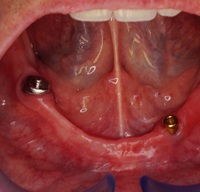

Pacjentka głosiła sie do naszego gabinetu do leczenia z osadzonym mikroimplantem w pozycji lewej dolnej dwójki. Siostrzany implant w pozycji prawej dolnej dwójki wypadł wcześniej, około 1,5 roku od implantacji. Odtworzono przedsionek i dziąsło rogowaciejące, osadzono dwa implanty, jednoczasowo z regeneracją kości. Dopiero na etapie ostatecznej rekonstrukcji protetycznej usunięto zachowany mikroimplant. To się nazywa motywacja do leczenia! Pacjentka przygotowywała sie na ślub prawnuczki :)